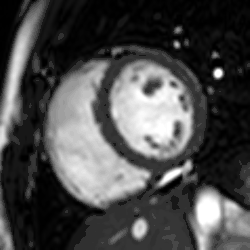

Enlarged right ventricle with poor function in a patient with repaired tetralogy of Fallot by CMR

Heart function using cine imaging

Functional and structural information is acquired using bSSFP cine sequences. These are usually retrospectively-gated and have intrinsically high contrast in cardiac imaging due to the relatively high T2:T1 ratio of blood compared to myocardium. Images are typically planned sequentially to achieve the standard cardiac planes used for assessment. Turbulent flow causes dephasing and signal loss allowing valvular disease to be qualitatively appreciated. The left ventricular short axis cines are acquired from base to apex and are used for quantifying end-diastolic and end-systolic volumes, as well as myocardial mass. Tagging sequences excite a grid pattern that deforms with cardiac contraction allowing strain to be assessed.